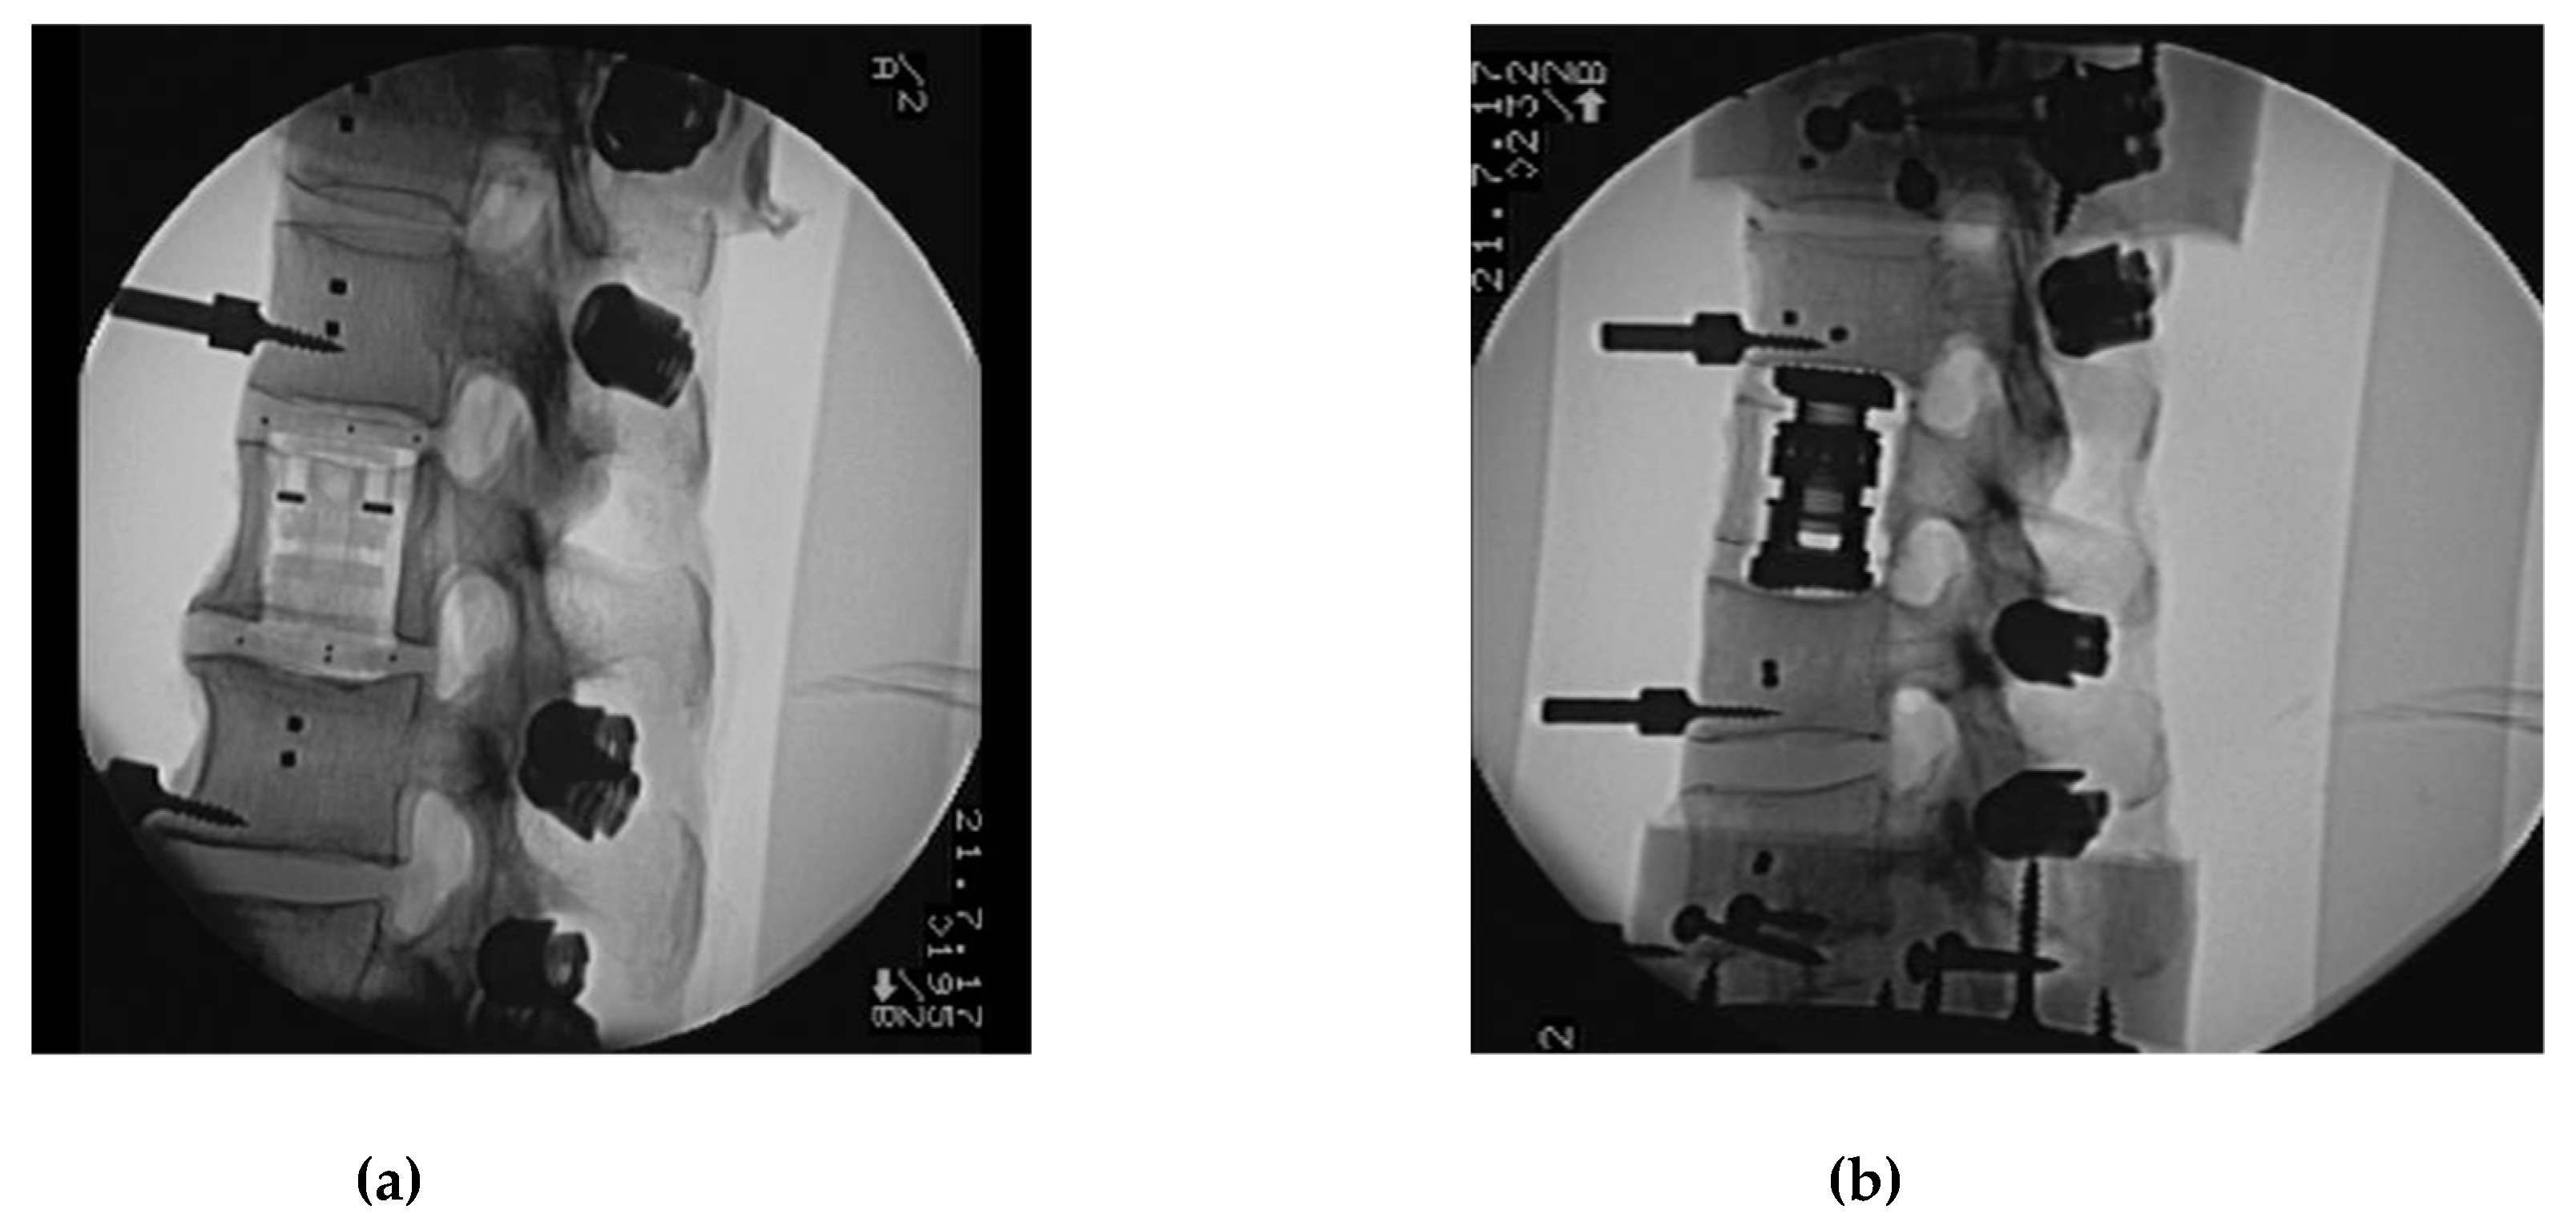

2. Materials and Methods

- (1)

- Flexibility test, Native (native):Corpectomy and instrumentation with VBR and pedicle fixation with CF/PEEK rod.

- (2)

- Flexibility test—CF/PEEK VBR instrumented with CF/PEEK rod (CF_CF):Change of posterior rod fixation to titanium rod.

- (3)

- Flexibility test—CF/PEEK VBR Instrumented with titanium rod, (CF_Ti):Change of VBR to titanium.

- (4)

- Flexibility test—titanium VBR instrumented with titanium rod (Ti_Ti):Addition of two cross connectors to the posterior rods dissecting the ligamentum supraspinale/interspinale.

- (5)

- Flexibility test—titanium VBR instrumented with titanium rod and 2 cross connectors (Ti_Ti_cc):Change to CF/PEEK VBR.

- (6)

- Flexibility test—CF/PEEK VBR instrumented with titanium rod and 2 cross connectors (CF_Ti_cc):Change rods to CF/PEEK.

- (7)

- Flexibility test—CF/PEEK VBR Instrumented with CF/PEEK rod and 2 cross connectors (CF_CF_cc).